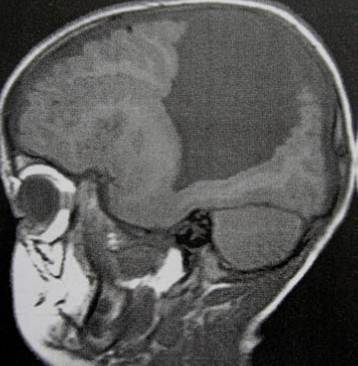

PERTANYAAN 44 - 45

Petunjuk: Seorang laki-laki usia 16 tahun dengan hasil MRI sebagaimana ditunjukkan di bawah ini, dirujuk ke kantor anda. Hasil pemeriksaan laboratorium pasien mengungkapkan bahwa dia menderita hipotirodisme, kekurangan kortisol dan kadar prolaktin sebesar 69. Keluarganya mengatakan bahwa mereka mencatat adanya berbagai perubahan perilaku dan baru-baru ini mengalami kenaikan berat badan. Mata kirinya tidak bisa melihat dan lapang pandangan temporal mata kanannya terputus.

C. Kraniofaringioma

Petunjuk: Seorang laki-laki usia 16 tahun dengan hasil MRI sebagaimana ditunjukkan di bawah ini, dirujuk ke kantor anda. Hasil pemeriksaan laboratorium pasien mengungkapkan bahwa dia menderita hipotirodisme, kekurangan kortisol dan kadar prolaktin sebesar 69. Keluarganya mengatakan bahwa mereka mencatat

adanya berbagai perubahan perilaku dan baru-baru ini mengalami kenaikan berat badan. Mata kirinya tidak bisa melihat dan lapang pandangan temporal mata kanannya terputus.

B. Efek Stalk